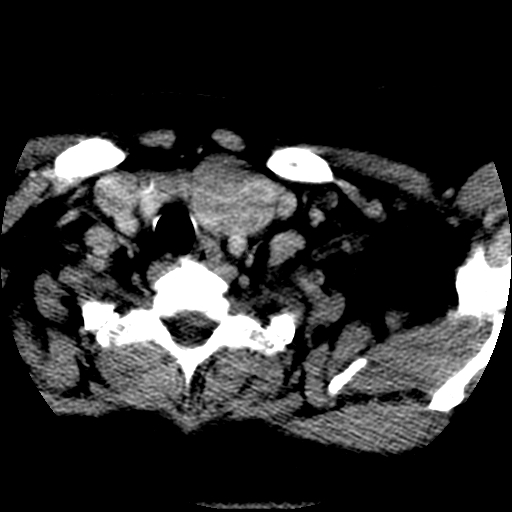

标题: CT25491:女,55岁,发现左侧甲状腺肿块一个月。 [打印本页]

女,55岁,发现左侧甲状腺肿块一个月,彩超示:甲状腺多发结节伴左叶结节液化。

边界清,无明显强化,考虑考虑甲状腺腺瘤

考虑左侧甲状腺结节性甲状腺肿,不排除甲状腺腺瘤。

考虑左侧甲状腺腺瘤囊变。